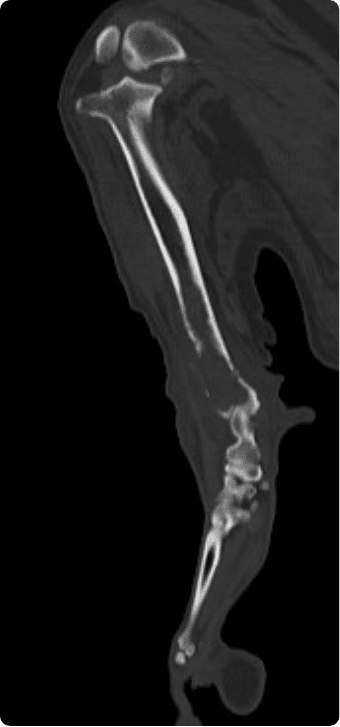

일산시티동물의료센터 영상의학센터는 최첨단 장비를 기반으로, 반려동물의 건강 상태를 보다 정확하고 신속하게

진단하는 핵심센터입니다. 고화질 CT와 초음파, 디지털 엑스레이, 투시촬영기기(C-arm)을 사용해

고해상도 영상과 정밀한 분석을 통해 질병의 조기 발견과 맞춤 치료 방향 제시를 목표로 합니다.

빠른 촬영속도를 통해 마취시간을 최소화 하며, 선명한 3차원 영상을 구현합니다.

종양, 전이평가, 선천적 혈관 기형 등 여러 질환의 조기 발견 및 환자상태를 평가합니다.

골절, 골종양 등